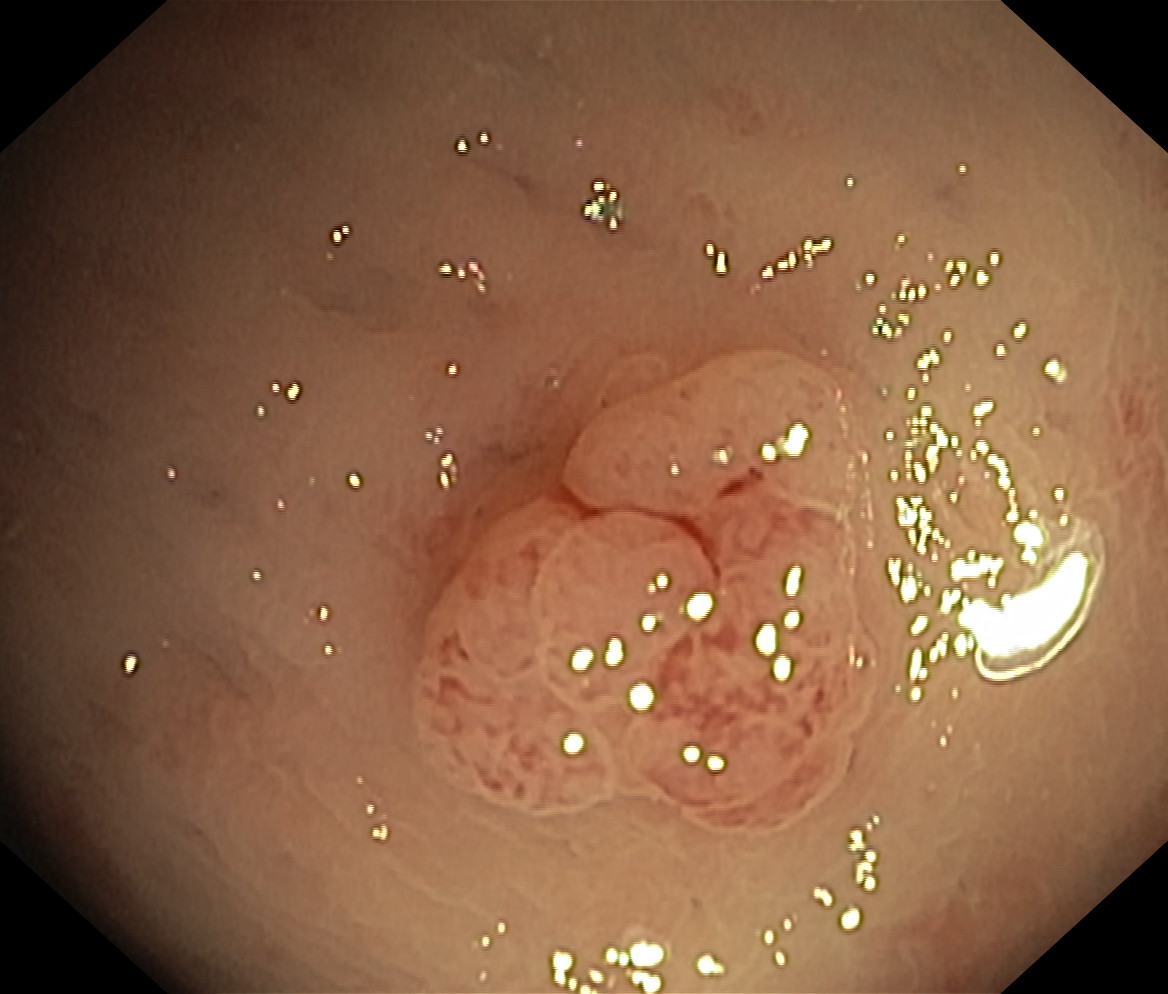

Polipy